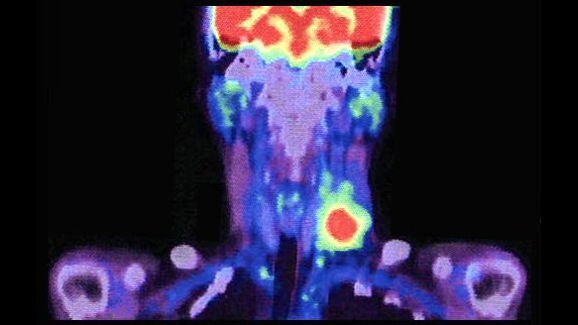

Екип от учени е успял да идентифицира с точност сентинелния лимфен възел – първия лимфен възел, който се засяга при туморни образувания – при плоскоклетъчен карцином в лицево-челюстната област (HNSCC), посредством нов радиотрейсър. Това откритие представлява значителен напредък за редуциране на усложненията, причинени след шийна дисекция на пациенти с тумори в лицево-челюстната област.

Използваният радиоактивен изотоп за образна диагностика, 99mTc–tilmanocept, е одобрен от Американската администрация по храните и лекарствата FDA през 2013 г. под търговското наименование Lymphoseek. Към момента се използва за локализиране на лимфни възли при пациенти с рак на гърдата, меланома или плоскоклетъчен карцином на устната лигавица, които претърпяват хирургични интервенции за отстраняване на лимфните възли, към които се дренират заболелите тъкани. Пример за подобни хирургични интервенции е селективната шийна дисекция.

Изследователи от САЩ са открили, че тилманосептът може с точност да идентифицира сентинелните възли при HNSCC, което е сложен процес, тъй като в областта на шията се намират до 150 лимфни възела. По тази причина с новия трейсър броят на пациентите с HNSCC, които понастоящем претърпяват селективна шийна дисекция, може значително да бъде намален.

С цел да се изпита ефективността на тилманосепта при карцином в лицево-челюстната област учените провели изследване сред пациенти с HNSCC в начален стадий в 12 различни медицински центъра в САЩ. Трейсърът бил инжектиран на общо 83 пациенти с планирани шийни дисекции. Изследователите успели да идентифицират и отстранят поне по един сентинелен лимфен възел при 81 от пациентите.

В сравнение с проучвания, които използват стандартни радиоколоиди, биопсията на сентинелните лимфни възли с употреба на тилманосепт гарантира висок процент на идентифициране и нисък процент на фалшиво отрицателни резултати по отношение на лимфните възли в устната кухина, като така спомага точното прогнозиране на разпространението на рака.